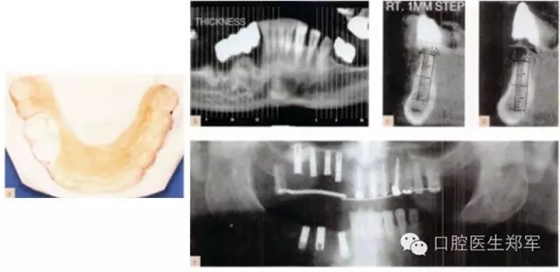

圖10 a 下頜影像和外科導(dǎo)板。b-d 下頜CT中放射導(dǎo)板的位置 e 種植后的影像圖片 |

圖11 a和b 種植體基臺和基牙的預(yù)備。c 再次評估暫時修復(fù)體并確認其功能、美學(xué)和穩(wěn)定性。d根據(jù)回切硅膠導(dǎo)板和暫時修復(fù)體交叉上牙合架技術(shù)修整最終修復(fù)體蠟型。 |

圖12 a和b最終修復(fù)體(圖由修復(fù)學(xué)專家Dr 0 Gelfan, Professor Z Artzi , and Mr B lndig.提供) |